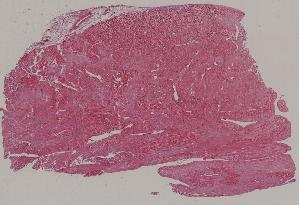

47. Myocardial infarction